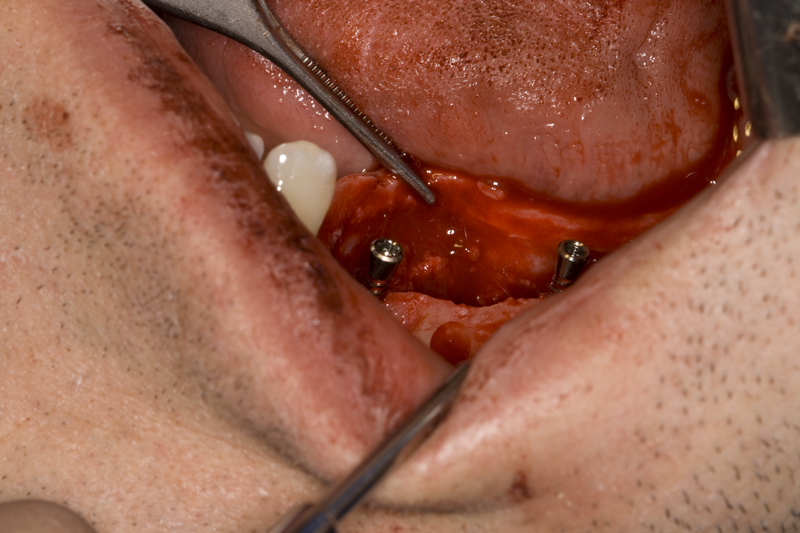

С фрезата за автогенна кост се извършва много бързо и лесно отнемане на

кортикалната кост

Tent screw - винтове за

фиксиране на титановата мрежа

Около винтовете се поставя костозаместител, добре е да се размеси с

автогенна кост